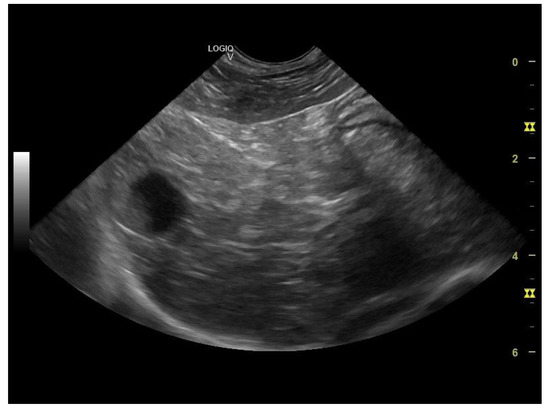

The liver appeared of normal size with non-homogeneous parenchyma, with multiple hyperechogenic strands diffusely dispersed throughout the parenchyma giving it a “Swiss cheese” appearance, with a slightly irregular outline and poorly distinguishable vascular walls (Figure 6 and Figure 7a,b). The gall bladder had a fine hyperechoic wall with anechoic content accompanied by hypoechoic, mobile, gravitationally dependent sediment in reduced quantity.

Figure 7. (a) Liver—non-homogeneous parenchyma (microconvex transducer). (b) Liver multiple hyperechogenic strands diffusely dispersed throughout the parenchyma—“Swiss cheese” appearance (linear transducer).

The ultrasonographical aspect of the liver as well as the normal size of the organ combined with the Swiss cheese-like appearance of the parenchyma corroborates the diagnosis of hepatocutaneous syndrome. Another differential diagnosis in absence of the dermatological findings could have been that of chronic hepatitis/liver cirrhosis, although the liver is reported to be reduced in size in these common conditions.